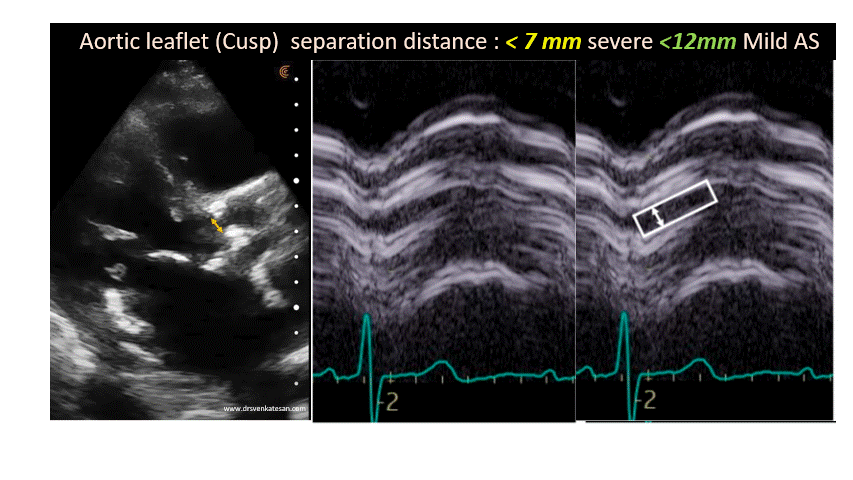

Mximal aortic leaflet separation (MACS) in M mode was identified as the distance between the inner edges of the tips of these structures at mid systole in the parasternal long axis view. Cuspal separation is also measured in 2D echocardiography from the parasternal long axis view and the average of the two values was taken as the MACS. 2D is more reliable than M-Mode. One might make it further simple by taking only 2D measurment. (In one way. it can be thought of as a 2-D equivalent to of vena- contracta in regurgitant lesions)

Maximal cusp separation distance is a quick way to assess the severity of AS, that avoids the doppler angulation errors. Further,i f we can take cusp separation distance as the diameter of the aortic valve orifice, ( assuming it is a circle) , then we can straight away calculate the EOA. using πr². Some one should do this analysis.